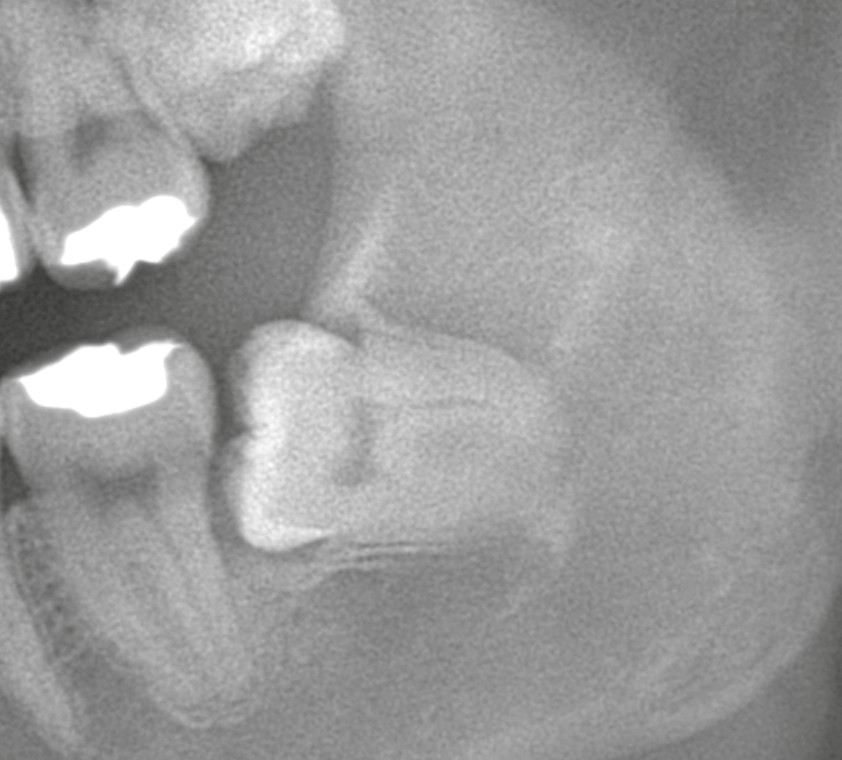

術前のCT検査にて、歯の根が下歯槽神経と接している所見が確認されました。下歯槽神経は、下唇や顎の感覚を司る大切な神経です。そのため、術後にしびれ(麻痺)が残るリスクがあることを事前にご説明しました。

1回目の処置では歯冠(歯の頭の部分)を分割・除去し、同時に歯周靭帯を切断。歯が少しずつ動きやすい環境をつくります。

その後、約3ヶ月間経過を観察しました。

3ヶ月後のレントゲンでは、歯がわずかに移動し、下歯槽神経との距離が確保されたことを確認。そこで2回目の外科処置として、通常の埋伏抜歯を実施しました。